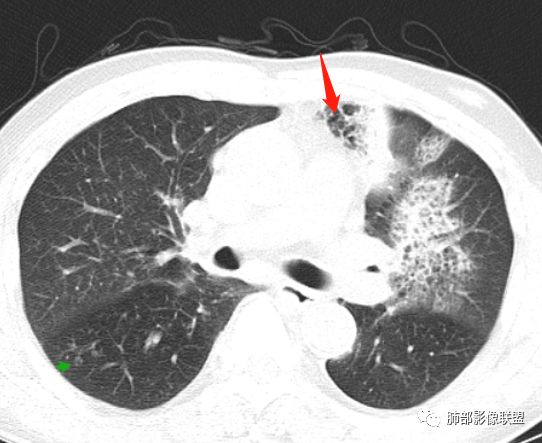

背段支气管有问题,局部有结节

左肺上叶病灶长轴与支气管走形一致,提示沿支气管分布病变,倾向于炎性,大家可能怀疑这个病例是来源于胸膜下为主的,胸膜下来源首先整体是来源于胸膜下,与胸膜下之间没有间隙,而这例与胸膜下有间隙。而且这个病变是沿支气管朝外蔓延的,而胸膜下来源的是朝内蔓延的,唯一给我们错觉的是靠近纵隔胸膜这个地方有问题。但是靠近纵隔胸膜这个位置实变不是靠近胸膜实变,它边缘收缩的,没有膨隆的迹象。我们看到里面支气管直达远端稍扩张,是以中央间质为主、小叶间隔朝外蔓延,有间质也有实质病变,走向是沿中央间质方向走的,我个人倾向炎性病变。    问题是右下叶病灶怎么解释?右隔上、右肺门各有一个结节。这个病人有急性咳嗽、胸痛的病史,还有糖尿病病史,周围渗出比较明显,应该警惕炎性病变,要警惕克雷伯杆菌、结核、金葡菌霉菌,因为糖尿病人经常好发这些病菌感染。那么右下叶病变怎么考虑?能不能一元论?    左肺病灶是一个急性渗出为主的病变,一个急性感染的迹象;右肺下叶背段结节,没有看到支气管,增强图支气管壁增厚,局部小结节,呈分叶状,支气管堵塞,没有粘液栓样指套样改变,但是里面有强化,我倾向于癌,其次待排结核。我还是倾向于癌的可能性,恶性可能性大一些,可惜我看不到支气管腔内。还考虑有没有淀粉样变性的问题,弥漫钙化灶最常见的一个是结核,另一个是淀粉样变性。叶段支气管壁有弥漫增厚的迹象。所以淀粉样变性跟结核都要考虑。

鳞癌起源于支气管粘膜,是气道中最常见的恶性肿瘤,易造成支管壁增厚,并突入腔内形成结节,造成狭窄、阻塞或截断;早期鳞癌表现为沿支气管生长的梭形结节或局限性增厚,辖区内常出现阻塞性炎症,这样的病灶赢多平面重建并仔细观察支气管改变;如果有支气管壁偏心性增厚伴管腔狭窄或腔内结节形成,都要想到早期鳞癌的可能性,复查或内窥镜检查是必要的。

鳞癌好发于中老年人,与吸烟关系密切,如果发现不易吸收的,或同一部位反复无常局限性肺炎,我们应当仔细观察支气管壁的病变除外阻塞的可能;该病例右肺下叶背段及左肺上叶支气管有肿块及管壁的增厚,应当想到恶性可能。